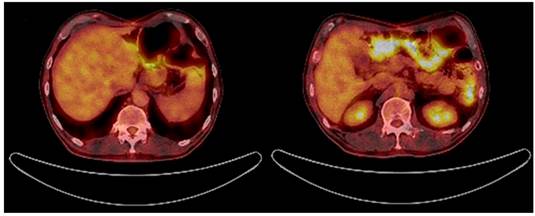

5 meses después de la cirugía, una nueva TAC toracoabdominal (el 11 de abril de 2018) reportó hígado de tamaño, morfología, densidad y contornos normales, sin lesiones focales y sin otras lesiones de extensión tumoral (Figura 1D). Posteriormente, asistió a controles y se encontró asintomático con leve hipoacusia y cambios de pigmentación en la piel por la quimioterapia. Una tomografía por emisión de positrones (PET scan) tomada el 17 de septiembre de 2018 no mostró evidencia de lesiones tumorales (Figura 3) y una resonancia magnética nuclear del 28 de octubre de 2018 tampoco evidenció lesiones sospechosas de malignidad en la anastomosis esofagoyeyunal ni lesiones a nivel del parénquima hepático. 18 meses después del diagnóstico inicial, el paciente se encuentra asintomático y no tiene signos que indiquen recaída tumoral. El estudio, tratamiento y seguimiento anteriormente mencionados se esquematizan en la Figura 4.

Dada la respuesta favorable al tratamiento instaurado por la desaparición de las lesiones hepáticas corroborado con imágenes y por una laparoscopia, al paciente se le realizó una gastrectomía total con linfadenectomía D2 con intención curativa. El resultado de la sobreexpresión del HER2 fue positivo en el espécimen quirúrgico. Después de la cirugía, recibió también trastuzumab como monoterapia y logró tener control de su enfermedad por 18 meses desde el diagnóstico inicial, con un PET scan negativo.